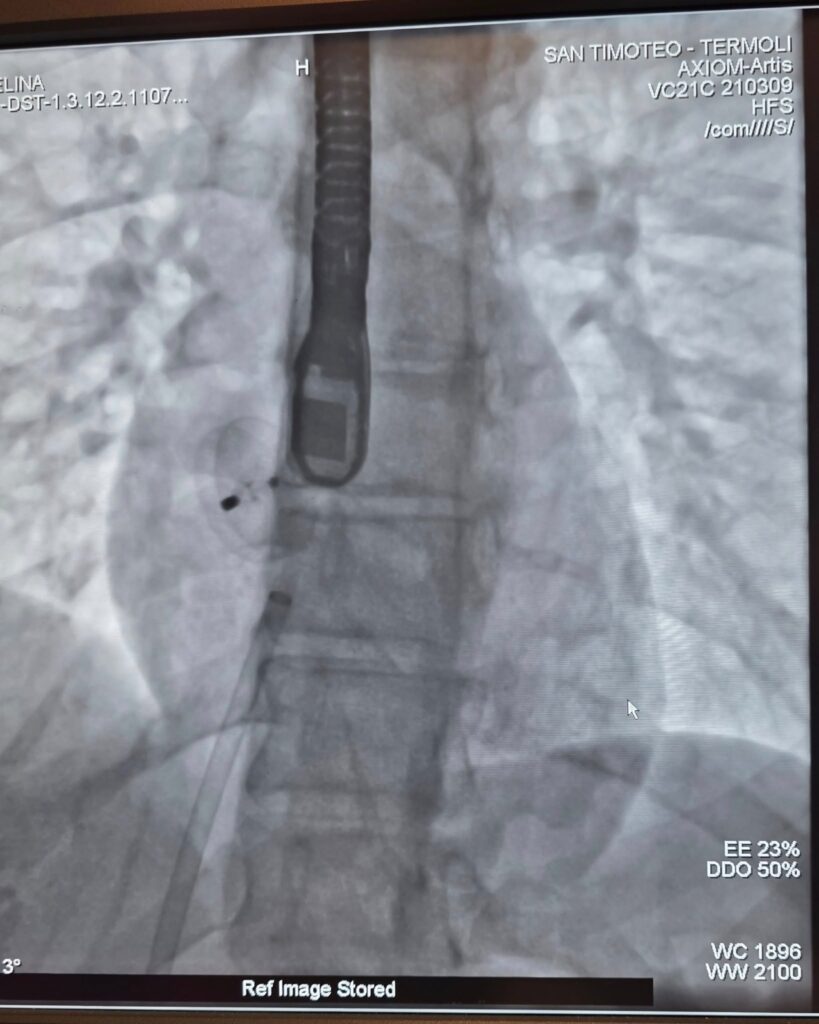

Cardiologia al San Timoteo di Termoli sempre più efficiente: effettuate procedure con tecniche mini-invasive